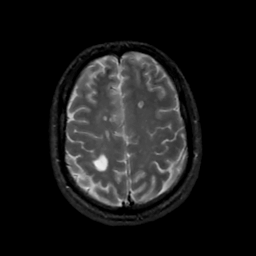

MR Study #12, May 12, 1991 -- Slice #38